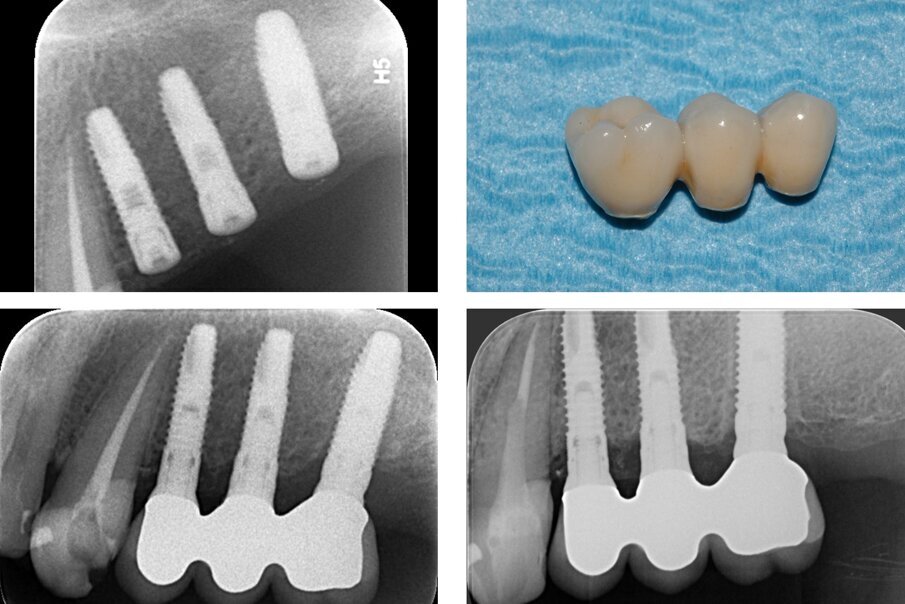

La cavità è stata quindi parzialmente riempita utilizzando un sostituto osseo di origine equina in granuli (Osteoxenon, Bioteck, Arcugnano), idratati con fisiologica sterile e miscelati con il particolato autologo prelevato precedentemente. Inserito il terzo impianto in posizione 2.6 (Stone, IDI Evolution, Concorezzo), il riempimento è stato completato utilizzando lo stesso sostituto osseo in granuli ed un’altra porzione del blocco impiegato in precedenza (Fig. 6). La finestra di accesso al seno è stata coperta con una membrana riassorbibile in collagene (Biocollagen, Bioteck, Arcugnano). Si è quindi proceduto alla sutura del lembo con una sutura non riassorbibile 5-0 (Monomyd, Butterfly, Cavenago). Non si sono osservate complicanze intra- o post-operatorie. La CBCT di controllo evidenziava il corretto posizionamento degli impianti, l’adeguato riempimento del seno, e la corretta interposizione del blocco osseo tra l’apice dell’impianto in posizione 2.7 e la membrana sinusale (Fig. 6). Dopo un adeguato tempo di guarigione, e seguite le usuali procedure di rimozione delle suture, scopertura degli impianti e condizionamento dei tessuti molli, a distanza di 4 mesi è stata consegnata la protesi definitiva in metallo-ceramica (Fig. 7). La paziente è stata controllata di seguito almeno annualmente. I controlli radiografici a un anno e a sette anni dall’intervento confermavano la conservazione dei livelli ossei perimplantari nel tempo, e la protesi appariva perfettamente funzionante (Fig. 7).

Fig. 7_Endorale al termine dell’intervento (in alto a sinistra); la protesi definitiva e due endorali di controllo scattate a un anno (in basso a sinistra) e sette anni (in basso a destra) dal posizionamento implantare. I livelli ossei perimplantari appaiono sostanzialmente invariati.